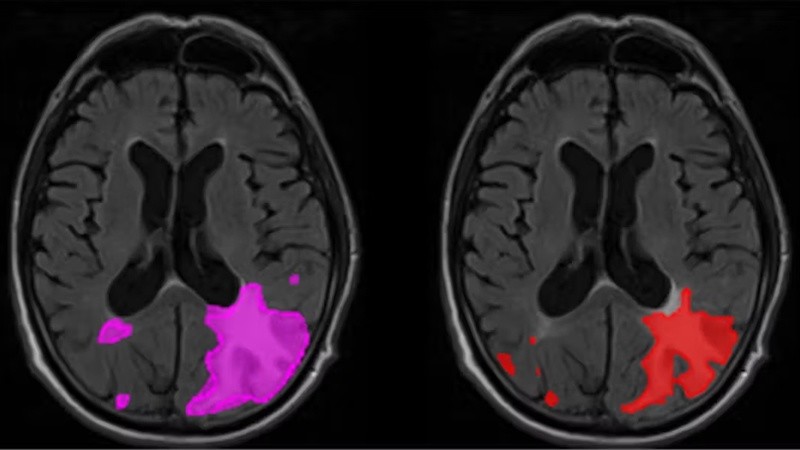

La interpretación de imágenes es tal vez una de las aplicaciones más maduras y visibles de la IA en la medicina. Los algoritmos de aprendizaje profundo, una rama más avanzada del aprendizaje automático, ya demostraron que pueden analizar radiografías, tomografías computarizadas, resonancias magnéticas y hasta muestras de tejido con una velocidad y precisión superiores a los procedimientos tradicionales, llegando incluso hasta elaborar informes detallados.

Un estudio publicado en junio de 2025 mostró cómo la incorporación de inteligencia artificial generativa en tiempo real dentro del sistema de imágenes permitió que los informes se redactaran automáticamente mientras el radiólogo analizaba los estudios, produciendo un borrador que luego era revisado por el especialista. Esta integración no solo mantuvo la calidad del diagnóstico, sino que además redujo drásticamente los tiempos de trabajo, con mejoras en la eficiencia que llegaron hasta el 40%. Además, esta herramienta incluye funciones de triaje automatizado, de modo que si el sistema detecta una condición grave, la marca y la compara con el historial del paciente para alertar al radiólogo de inmediato, incluso antes de que este haya revisado las imágenes.